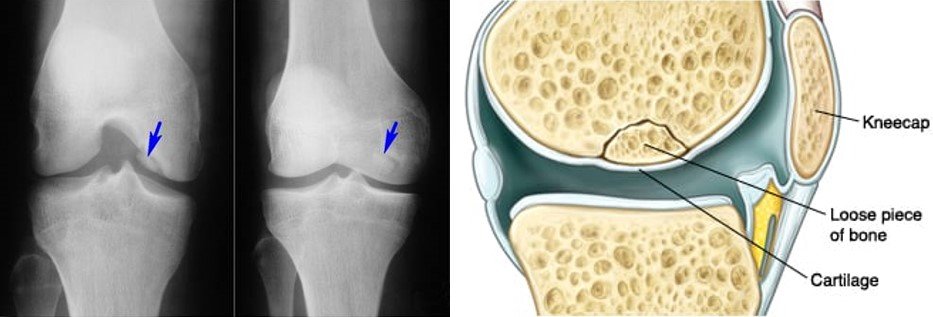

Почнемо з того, що хвороба Кеніга, більш відома науково як остеохондрит розсійка, являє собою стан, за якого частина кістки вкритої хрящем відшаровується — прямо всередині суглоба. Зазвичай ця біда коїться у коліні. Коли все отак тріщить, що може бути гірше?

І що ж у кінцевому рахунку? Без правильного лікування частинка кістки може повністю відірватися — приводячи до хронічного болю чи, навіть, втрати функціональності.

- Рентген: заморозити кадр, щоб побачити те, що приховано.

- МРТ: глибокий скан мозку сутності кістки і хряща.